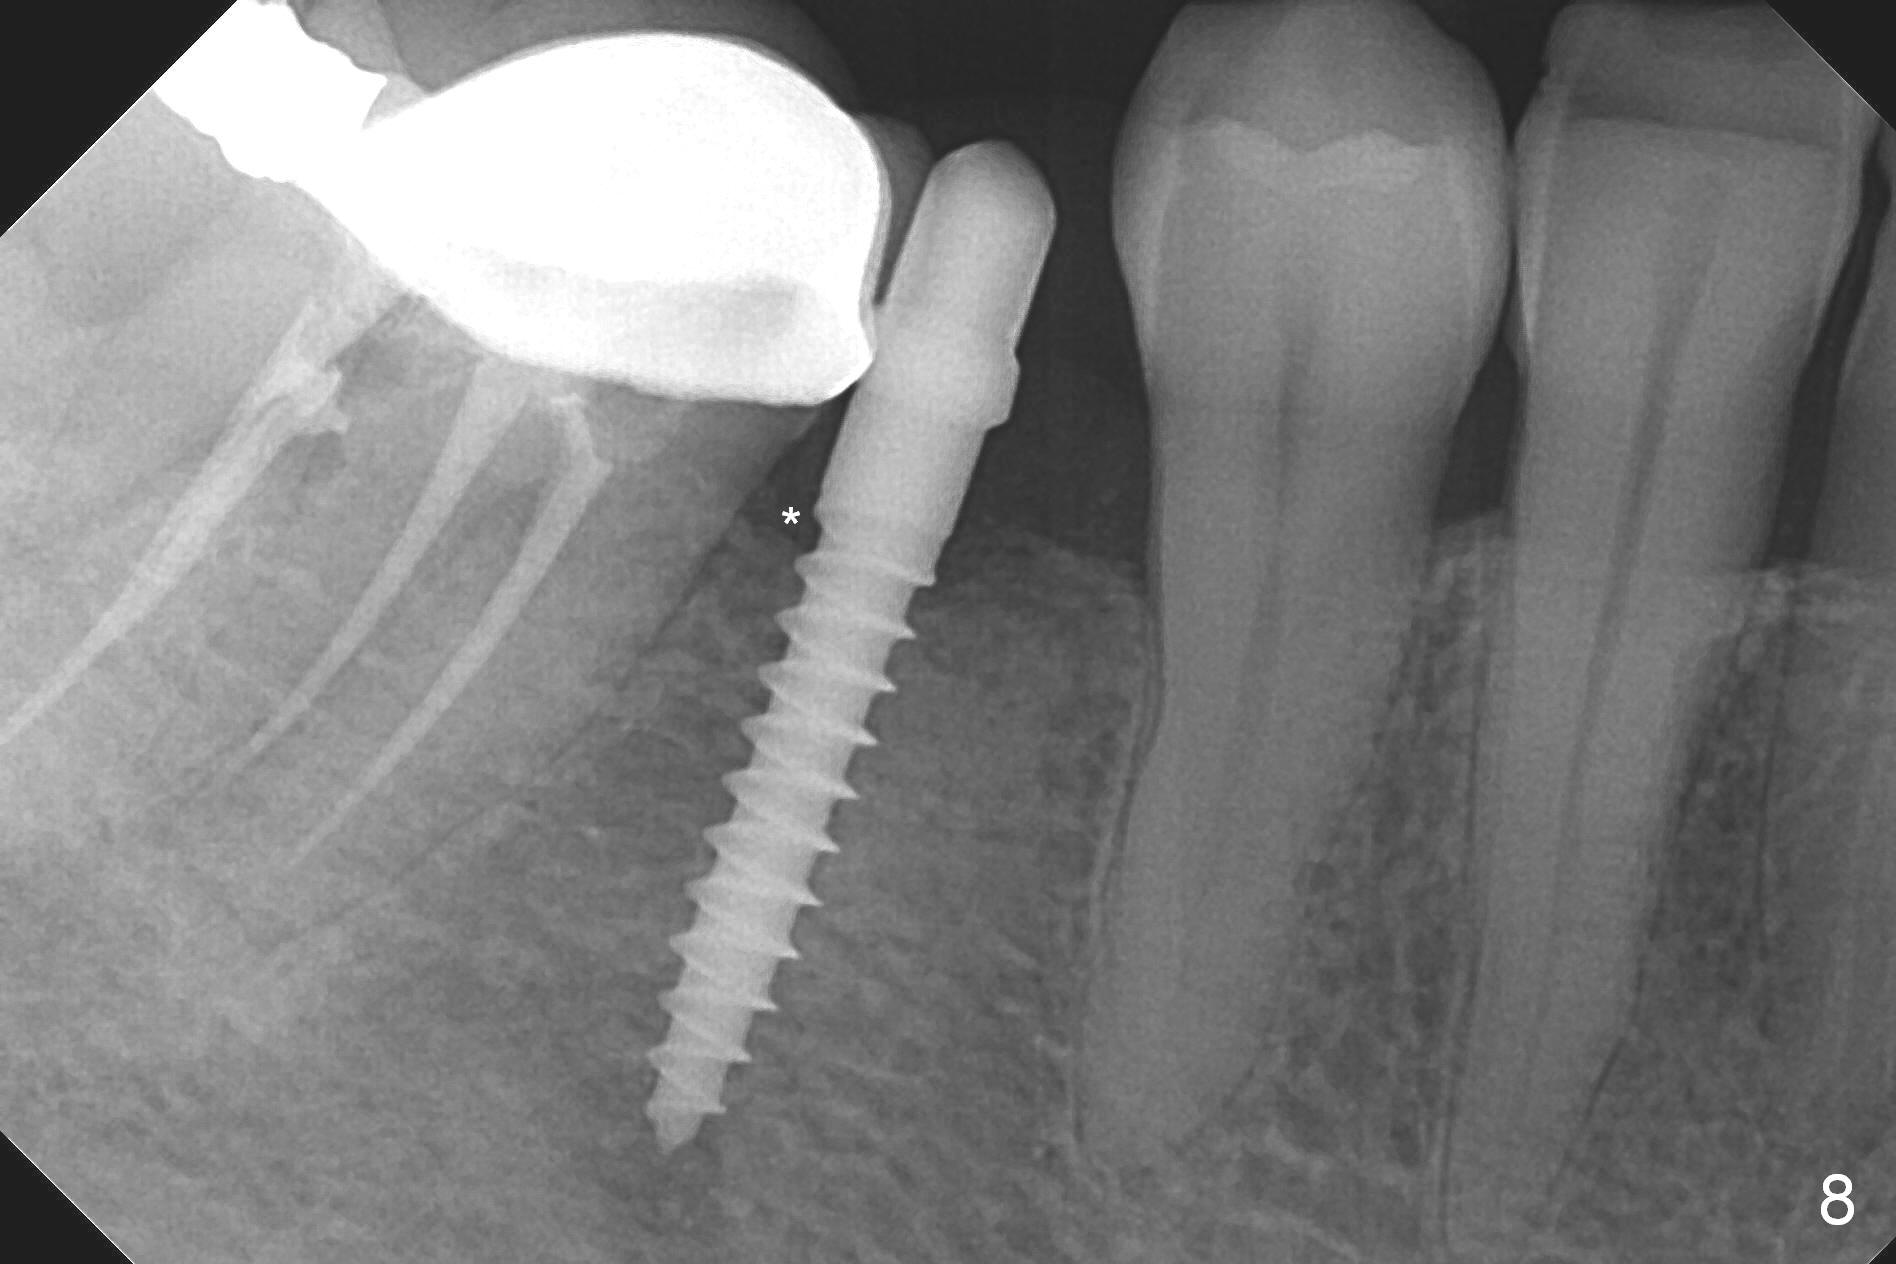

Preop photo shows the distal inclination of the tooth #28 (Fig.1).  The distal surface of the latter is reduced before incision for implant placement at #29 (Fig.2).  The buccolingual width is approximately 4 mm, as compared to 3 mm implant positioner (Fig.3).  After 1.2x10 mm osteotomy (Fig.5), the mesiodistal cortical bone is removed with a small high-speed fissural bur (Fig.4).  When a 2.5x12(2) mm 1-piece implant is placed (Fig.6), there is no buccal (Fig.7) or lingual plate perforation.  There is no postop paresthesia.  There is mild bone loss distal 4 months postop (Fig.8 *).  Take photos before and after permanent crown cementation to show increase in ridge width after bone graft and improvement in gingival health after provisional modification.  Take PA and/or BW post cementation to show that the distal bone resorption (Fig.8 *) is partially due to angulation.  No continuous bone loss 15 months post cementation (Fig.9).  There is mild bone resorption mesially 2 years 3 months post cementation (Fig.10).  The soft and hard tissues remain healthy 4 years 3 months post cementation (Fig.11,12).